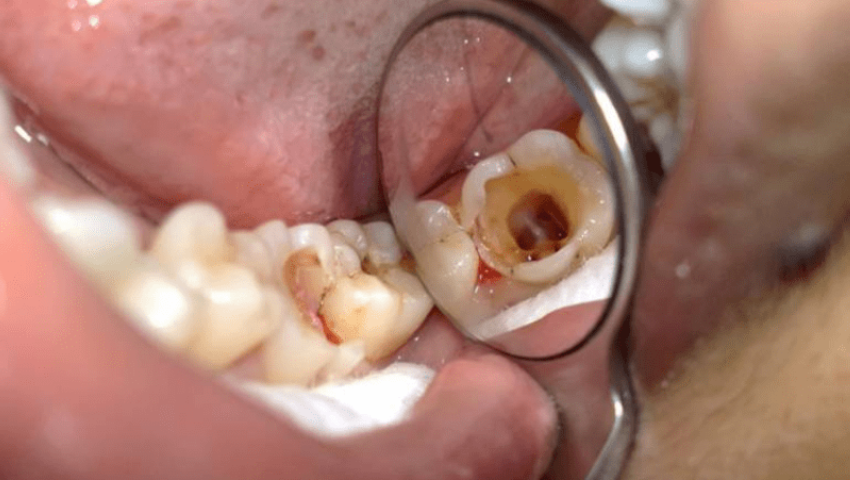

Viêm tủy răng số 7 được phân thành 3 giai đoạn, đó là: Viêm tuỷ hồi phục, viêm tuỷ không thể hồi phục, hoại tử. Trường hợp răng số 7 bị viêm tủy chuyển sang giai đoạn hoại tử thì lúc này các dây thần kinh trong răng cũng chết theo. Nếu chữa trị, nha sĩ buộc phải hút để loại bỏ tủy chết ra, sau đó trám bít ống tủy lại và phục hình răng cho người bệnh.

- Bước 1: Người bệnh chụp X – quang kiểm tra tình trạng tủy răng.

- Bước 2: Gây tê để giảm đau trong quá trình hút tủy.

- Bước 3: Đặt đế cao su vào khoang miệng để tách răng và nướu.

- Bước 4: Mở ống tủy, hút tủy viêm, hoại tử.

- Bước 5: Tạo hình ống tủy, sau đó bít trám ống tủy.

- Bước 6: Kết thúc quá trình điều trị và hướng dẫn bệnh nhân cách chăm sóc, hẹn lịch tái khám.